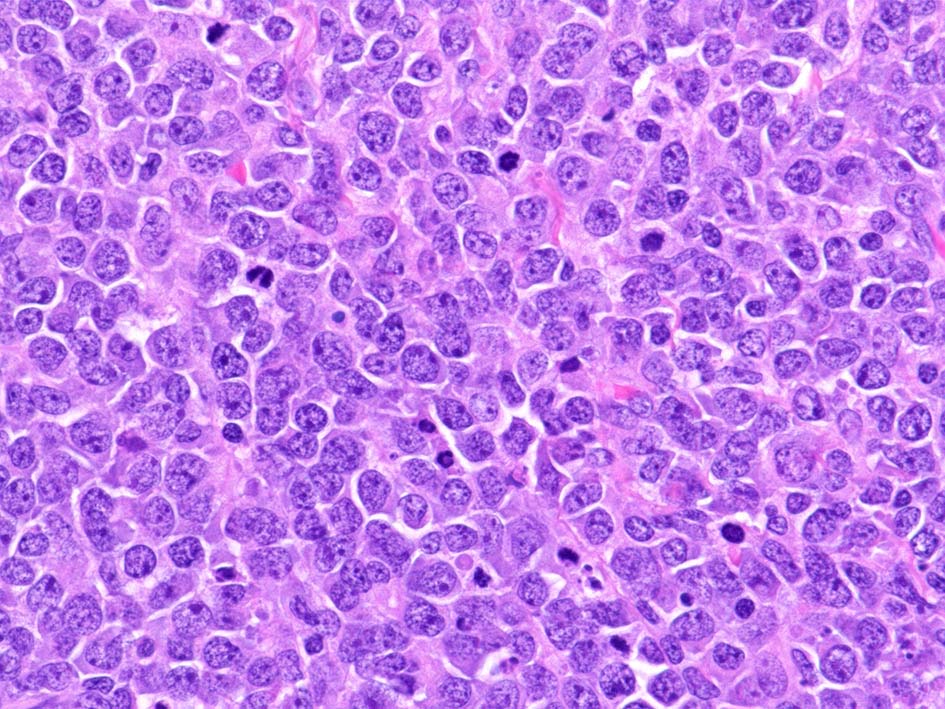

腫瘍内に壊死が認められる. 異型リンパ球の密な増殖により精細管は消失している.

腫瘍細胞はcentroblastic cells. mitosisやapoptosisが多い.